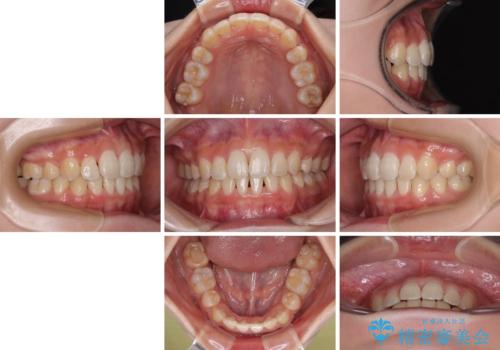

急速拡大装置 狭い骨幅を拡大した上で、口元の突出感を改善する抜歯矯正治療

- 前歯のデコボコと唇の閉じにくさを気にして来院された患者様です。

単純に上下左右の第一小臼歯4本を抜歯して口元の突出感を改善することも考えられましたが、上顎骨よりも下顎骨の幅が広いため、より良い咬み合わせを達成することを目的として、急速拡大装置を用いて上顎骨を拡大することとしました。